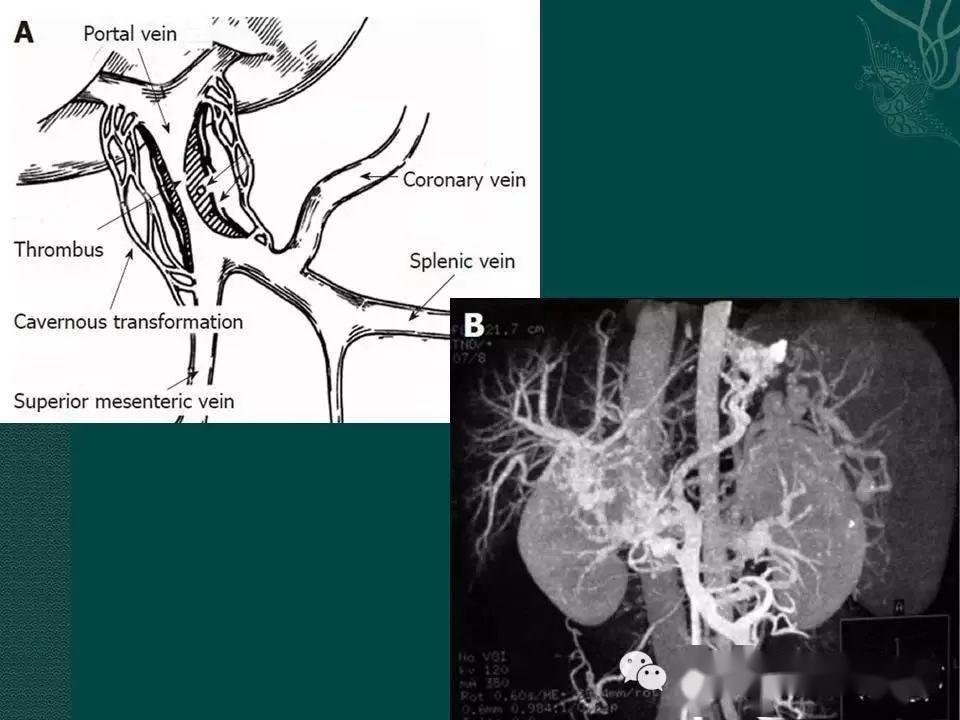

门静脉海绵样变性

门静脉海绵样变性的诊治ppt

临床提示:消化道出血,你会想到ctpv吗?_门静脉

病例3 胰腺体尾部囊腺癌ct增强 血管成像:脾静脉受侵蚀狭窄,门静脉左